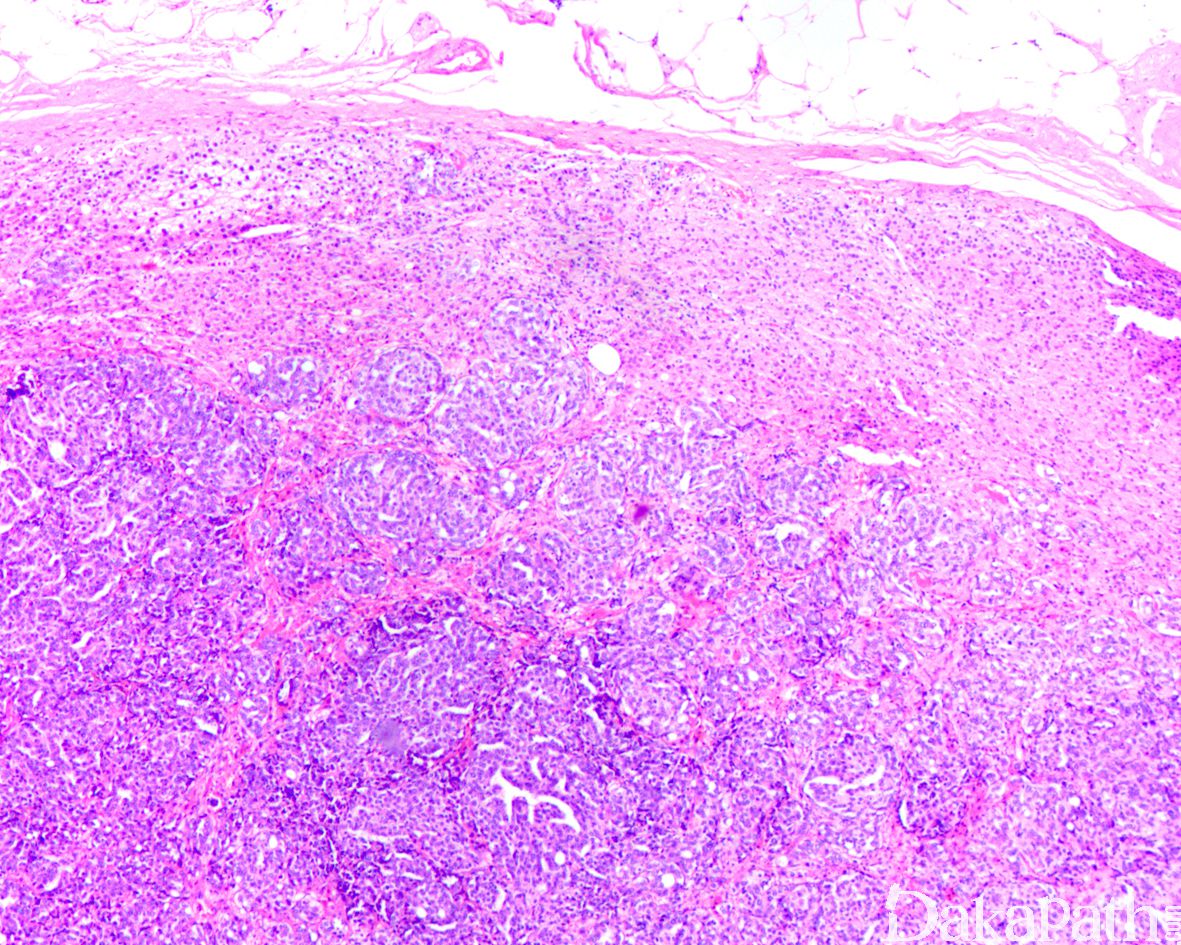

1,肾上腺是恶性肿瘤好发的转移部位,位居肝、肺、骨之后,转移到肾上腺的原发肿瘤最常见是乳腺,肺,肾,胃肠道,胰胆管等;半数以上类似双侧肾上腺,少见表现为孤立性转移灶;

2,组织学上,超过 90%以上为转移性癌为腺癌,常见较多的脉管内癌栓。肾细胞癌,肺的大细胞神经内分泌癌,肝细胞肝癌,黑色素瘤等转移至肾上腺可明显造成鉴别诊断困难;